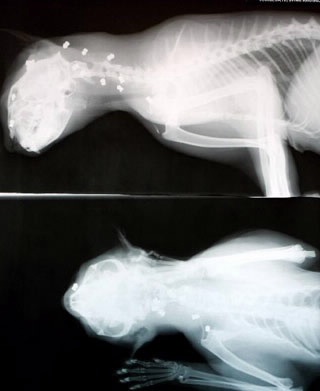

Hình chụp X-quang vết thương của Possum.

Chú mèo Possum, 2 tuổi, may mắn thoát chết sau khi chịu đựng 27 phát súng, trong đó có 2 phát trúng lưỡi và khoang mũi.

Cảnh sát đang điều tra kẻ tấn công man rợ. Còn chú mèo tội nghiệp sẽ phải tiến hành phẫu thuật để lấy những viên đạn ra khỏi cơ thể. Bà Jodi Mulley, chủ nhân của chú mèo đã gắp 5 viên đạn ra khỏi người nó, còn 7 viên nữa bị ghim trong da nên không thể nhìn thấy.

Người ta cho rằng chú mèo bị sập bẫy ở Porthsmith và bị bắn bằng loại súng săn đạn nhỏ. Một viên đạn gần đâm trúng tĩnh mạch cổ của nó.